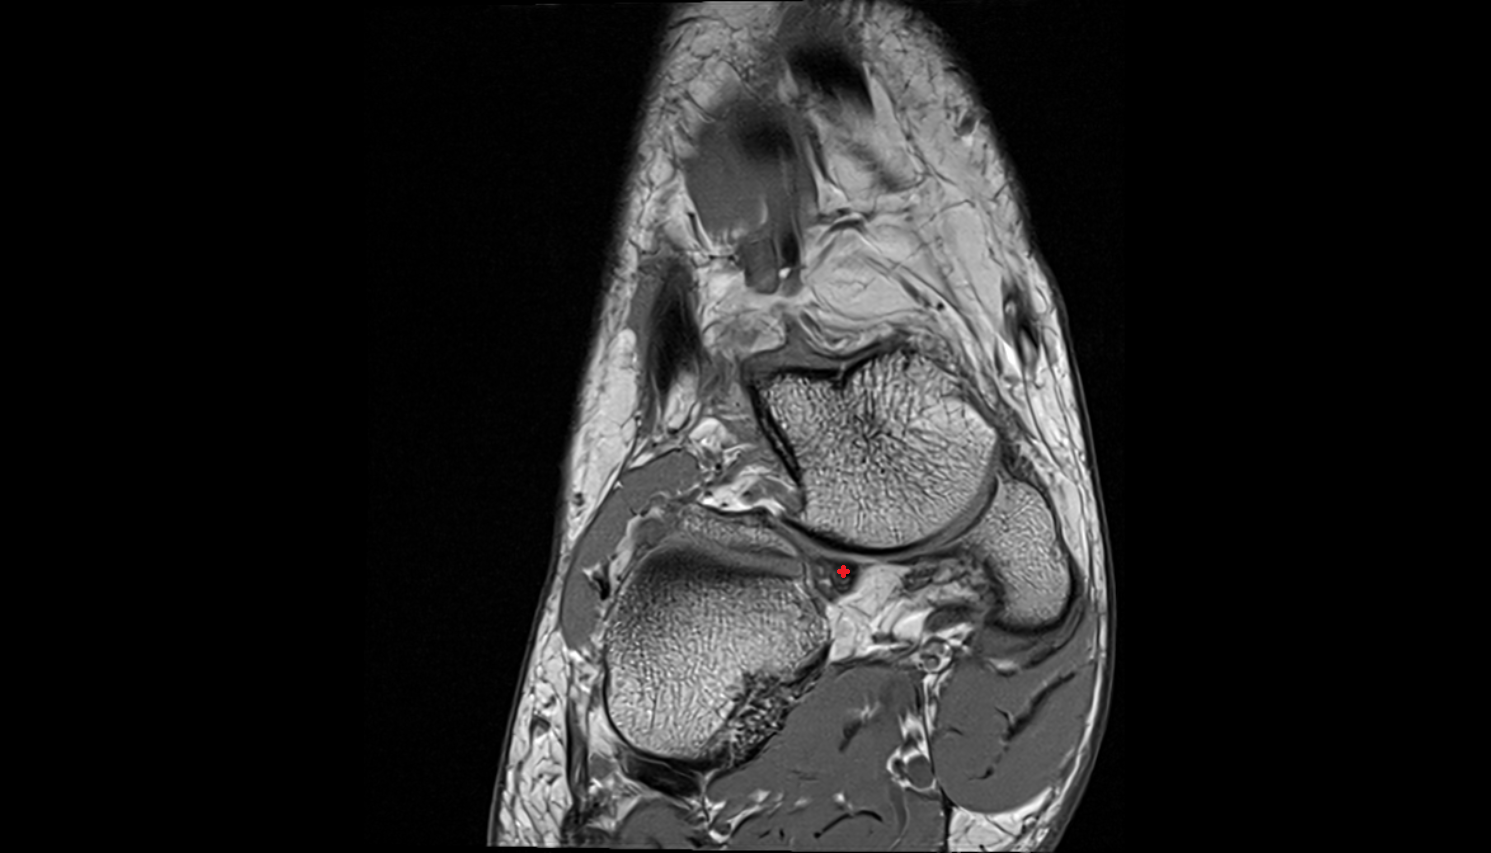

- Talus

- Head of talus

- Body of talus

- Neck of talus

- Posterior talar articular facet

- Calcaneus

- Ankle joint

- Talocalcaneal joint